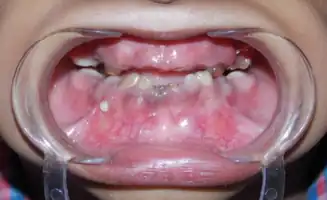

| Shows the severe underbite pattern that is a common development pattern in individuals with Tricho Dento Osseous Syndrome | |

In the oral cavity 100% of people diagnosed with TDO have taurodontism which is characterized by vertically enlarged pulp chambers at the expense of the roots of the teeth; the floor of the pulp chamber and furcation is moved apically down.[1] This is due to the failure of the Hertwig epithelial root sheath which maps the shape of the forming tooth roots during active differentiation. Amelogenesis imperfecta, an abnormal formation of the enamel or external layer of the crown of the tooth, may also be present where the tooth enamel may be thin or absent. There are several clinical subsets of amelogenesis imperfecta, but common to TDO is the hypoplastic-hypomaturation subtype;[3] the hypomaturation-hypoplastic is less common in individuals with TDO. The difference between the 2 dominant subtypes is the changes seen in the enamel matrix, and the phenotypic type that predominates. The hypoplastic-hypomaturation type of amelogenesis imperfecta with TDO occurs where the tooth enamel depicts a generalized pitted pattern, with open contacts between the teeth as well as an open bite. A smaller number of cases are of the hypomaturation-hypoplastic case type, in which the enamel structure is softer due to the under maturation of ameloblasts during development. Mandibular prognathism also called a severe underbite, is also a prominent feature in TDO. Prognathism defects are diagnosed based the level of severity that this condition interferes with being able to chew or speak properly.

Intra-oral view showing severly attrited teeth, visible pulp chambers and class III anterior occlusal relationship.